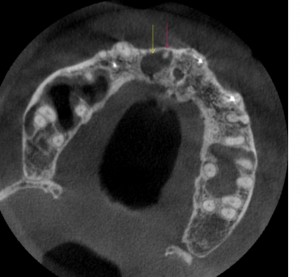

弁護士のBさんの上顎骨のCT水平断。前歯の欠損部にインプラントを入れたいが、隣の歯の根っこの先(ピンクの矢印)に膿の袋があり、これがインプラントを入れたい場所(黄色い矢印)に侵入して骨が溶けて空洞化(黒い部分)いる。まず、根っこの治療をしなければならない。